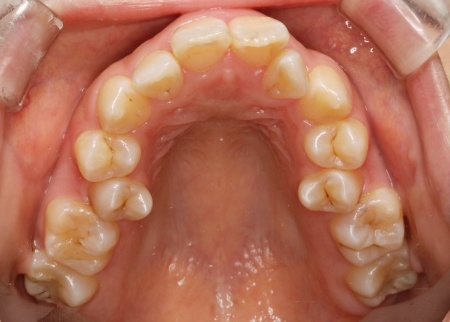

20代女性 ワイヤー矯正とマウスピース矯正を併用したハイブリッド矯正で歯並びを改善した症例

拝見したところ、上下の歯が正しく並ぶためのスペースが足りず、デコボコに生えていました。

とくに、犬歯が正しい歯並びから大きく飛び出した位置に生えており、いわゆる八重歯の状態です。

また、奥歯を噛み合わせた際に上下前歯が噛み合わず隙間ができる開咬(かいこう)も認められました。